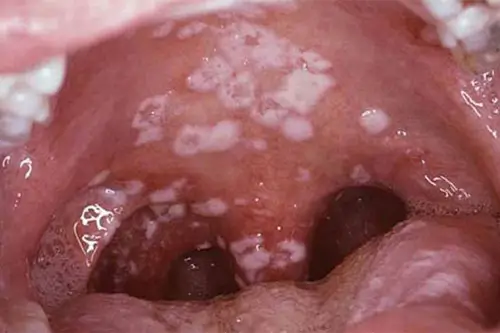

Triệu chứng lậu hầu họng

Rất thường gặp ở người quan hệ oral:

- Đau họng

- Họng đỏ

- Sốt nhẹ

- Không có triệu chứng (nhiều trường hợp)